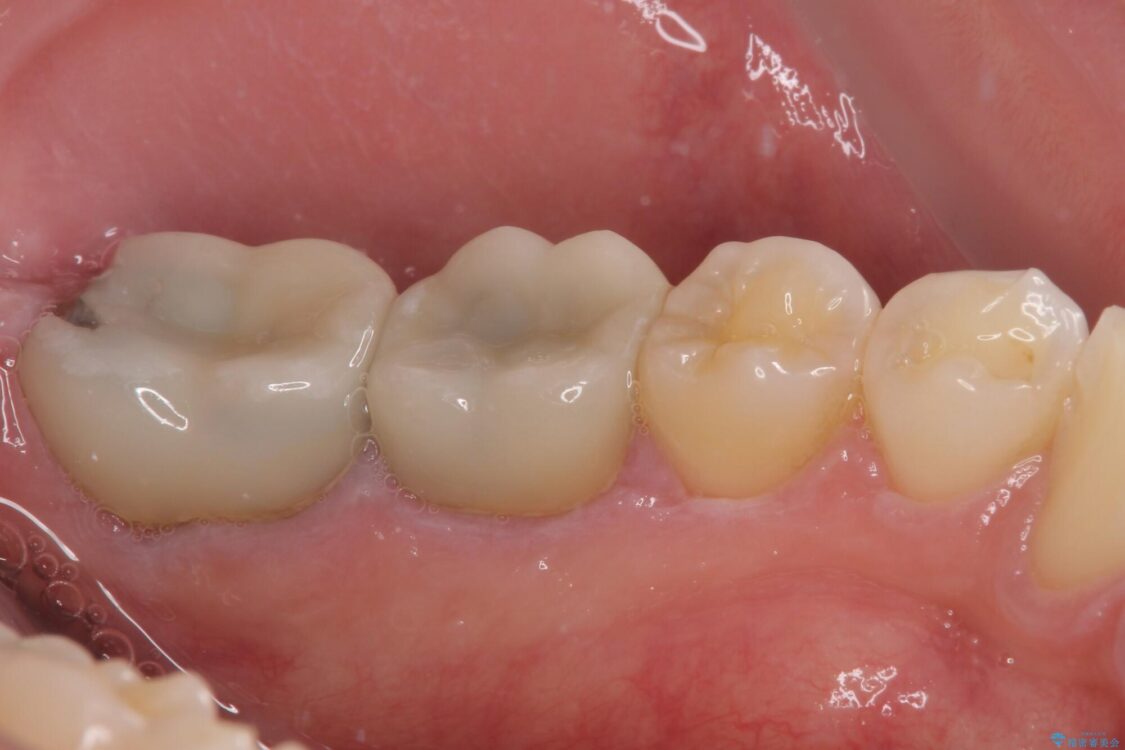

治療後

• 海外赴任前に治したい 割れてしまった奥歯のオールセラミッククラウン 治療後画像